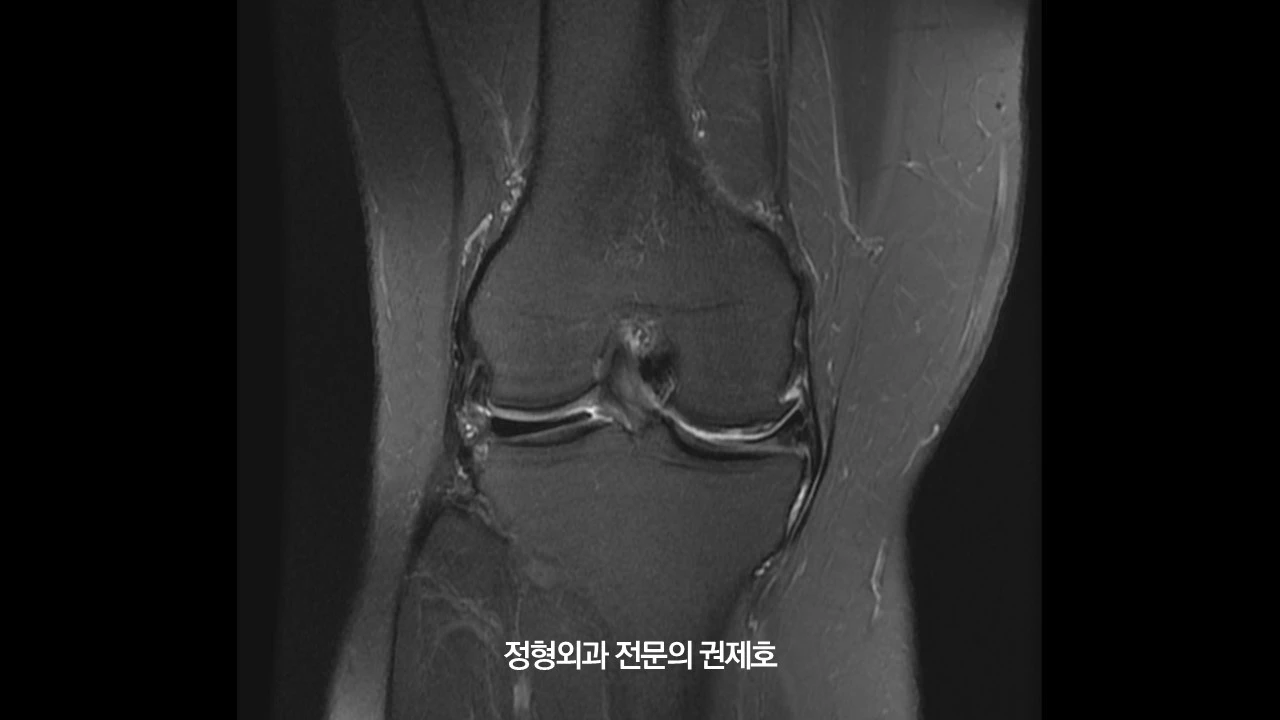

왼쪽 무릎 MRI를 보시게 되면 내측 반월상 연골판 골기시부 파열이 있으면서 오른쪽과 마찬가지고 연골 손상이 동반된 것을 아실 수 있습니다.